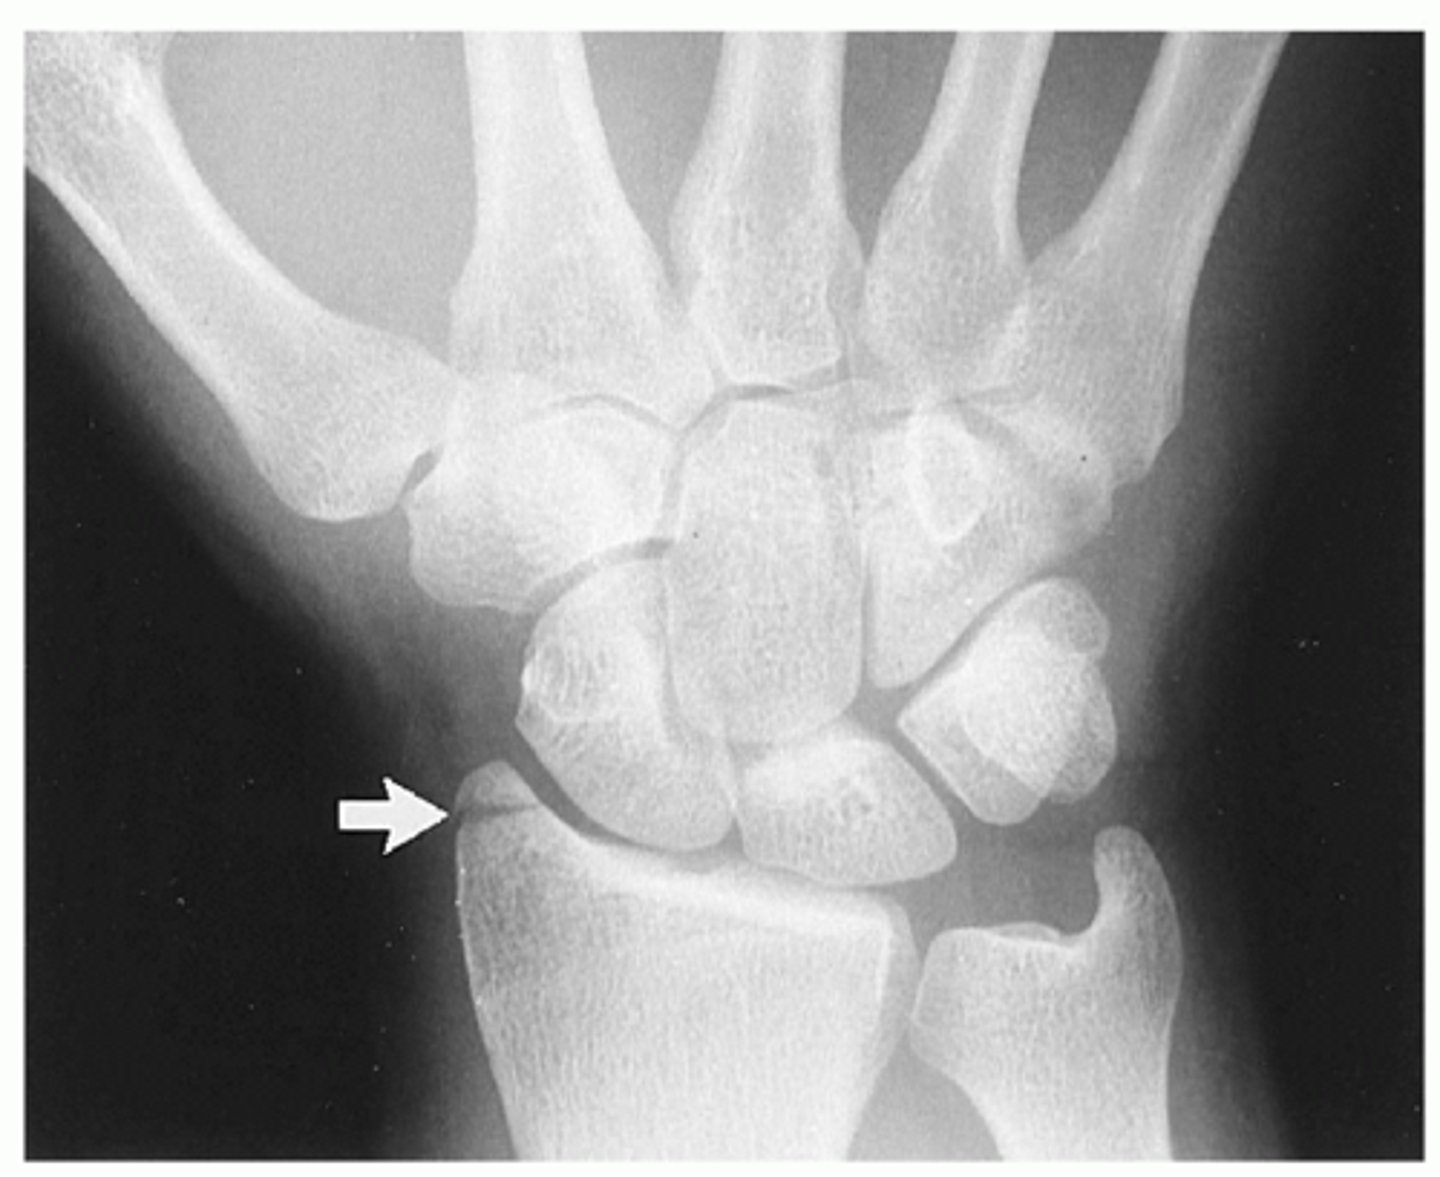

Intraarticular fracture of radial styloid process. Also called a chauffeur's fracture.

Hutchinson's fx